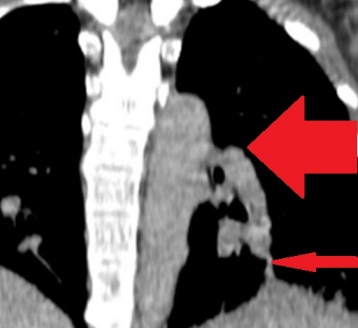

Different views of a double contrast-enhanced CT scan showing a left diaphragmatic hernia with an acute dilated stomach (Courtesy Dr. V. Penopoulos)